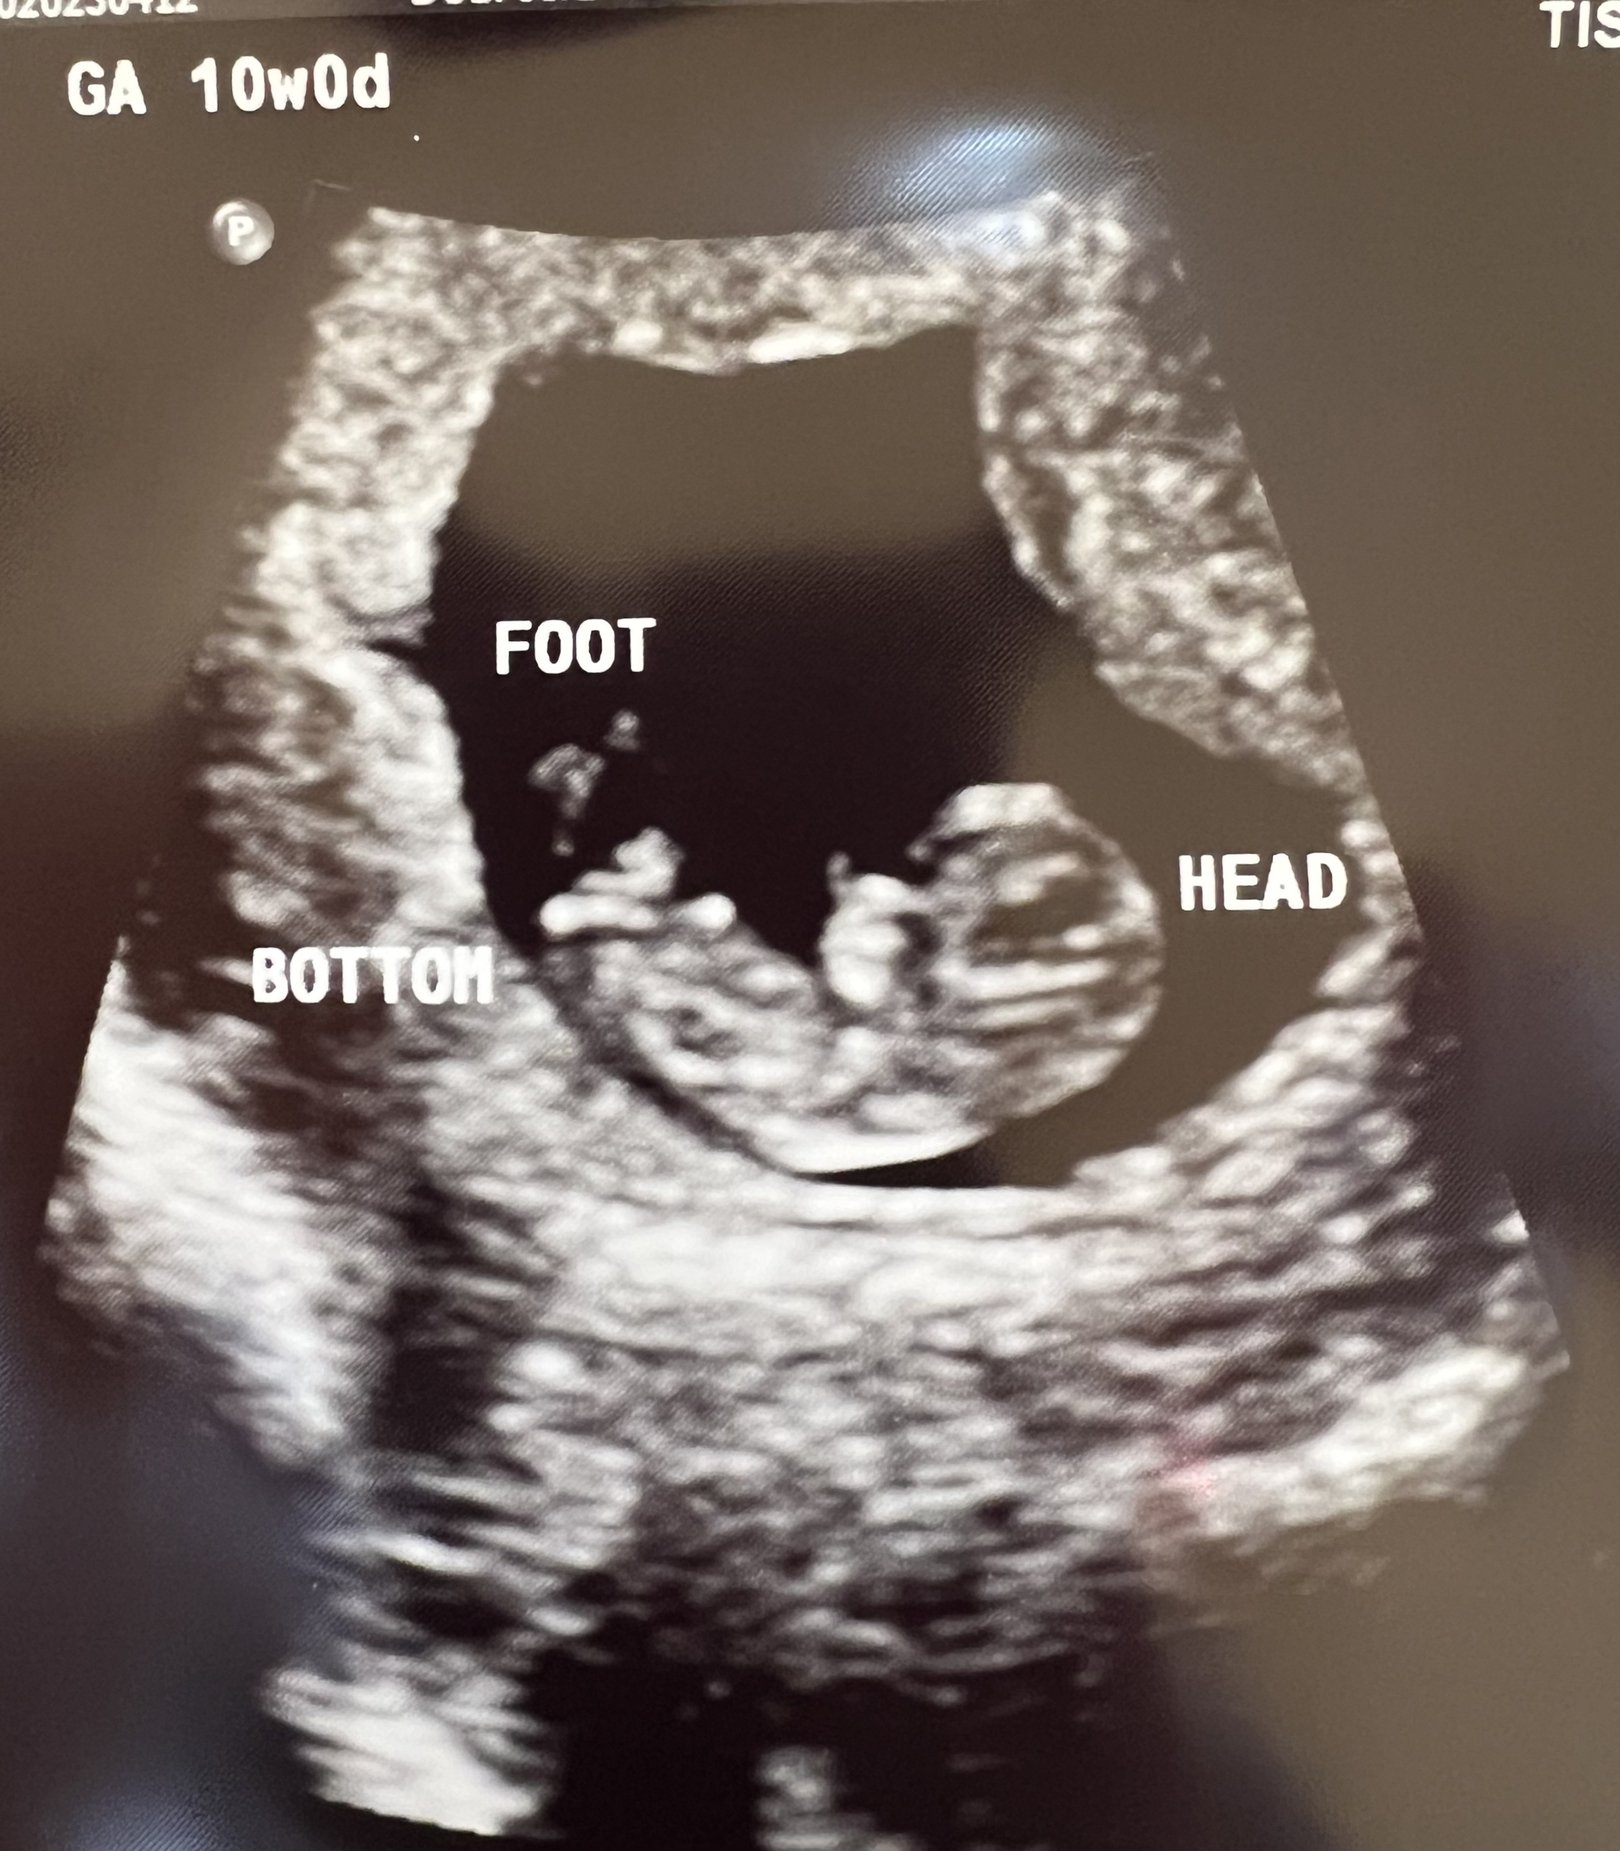

It's really real. They adjusted my due date by 1 day so I guess I'm now 9 weeks on the dot and due 11/2. Strong heartbeat at 178 bpm. Had a fun appointment explaining to all the new doctors that this is my 4th total pregnancy (2 viable, 1 mc) and we already have 4 kids. It took them a minute. 🤣

Crazy to see how big my uterus is in comparison lol.